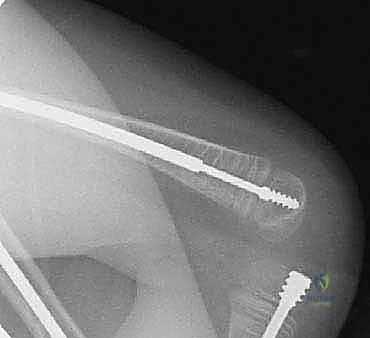

قبل العملية، يقوم الدكتور هطيف بإجراء دراسة شاملة لصور الأشعة السينية (X-rays) المأخوذة بدقة، لحساب زوايا التقوس بدقة متناهية، وتحديد نقاط بضع العظم (أماكن القص)، واختيار الحجم والطول المناسبين للمسمار التلسكوبي.

الخطوة الرابعة: إدخال المسمار التلسكوبي

بعد تقويم العظم وجعله مستقيماً كحبات المسبحة على خيط، يتم إدخال السلك الدليلي (Guide Wire). ثم يتم إدخال الجزء الخارجي (الأنثوي) من المسمار التلسكوبي وتثبيته في الجزء العلوي من العظم (Epiphysis).

بعد ذلك، يتم إدخال الجزء الداخلي (الذكري) من المسمار عبر الجزء السفلي من العظم وتثبيته في المشاشة السفلية. هذا التصميم العبقري يضمن حماية العظم بالكامل من الداخل.